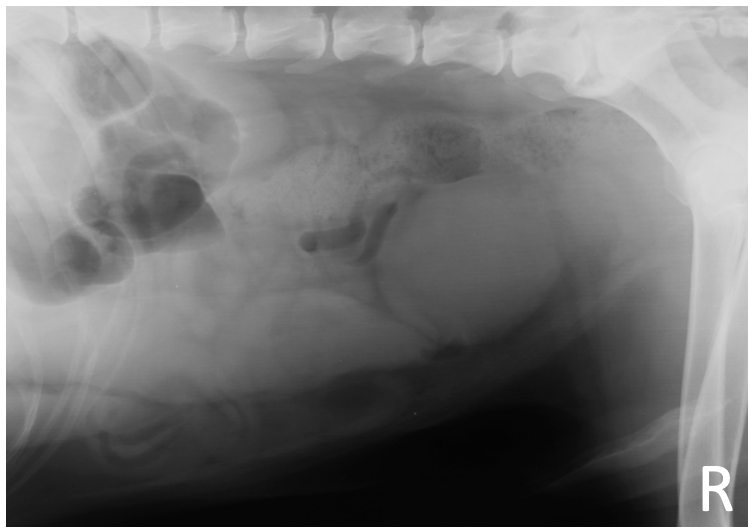

What is shown in these images?

prostatic neoplasia -enlarged prostate -indistinct mineral foci associated with prostatic parenchyma

What are the radiographic signs of prostatic neoplasia metastasis?

-sublumbar lymph node enlargement -"spondylitis" of caudal lumbar vertebrae -irregular new bone formation at the sacrum and pelvis

43

prostatic gland metastasis -prostatomegaly -severe enlargement of sublumbar lymph nodes -"spondylitis" of L3 to L6 -mineralization in soft tissues ventral to first caudal vertebra